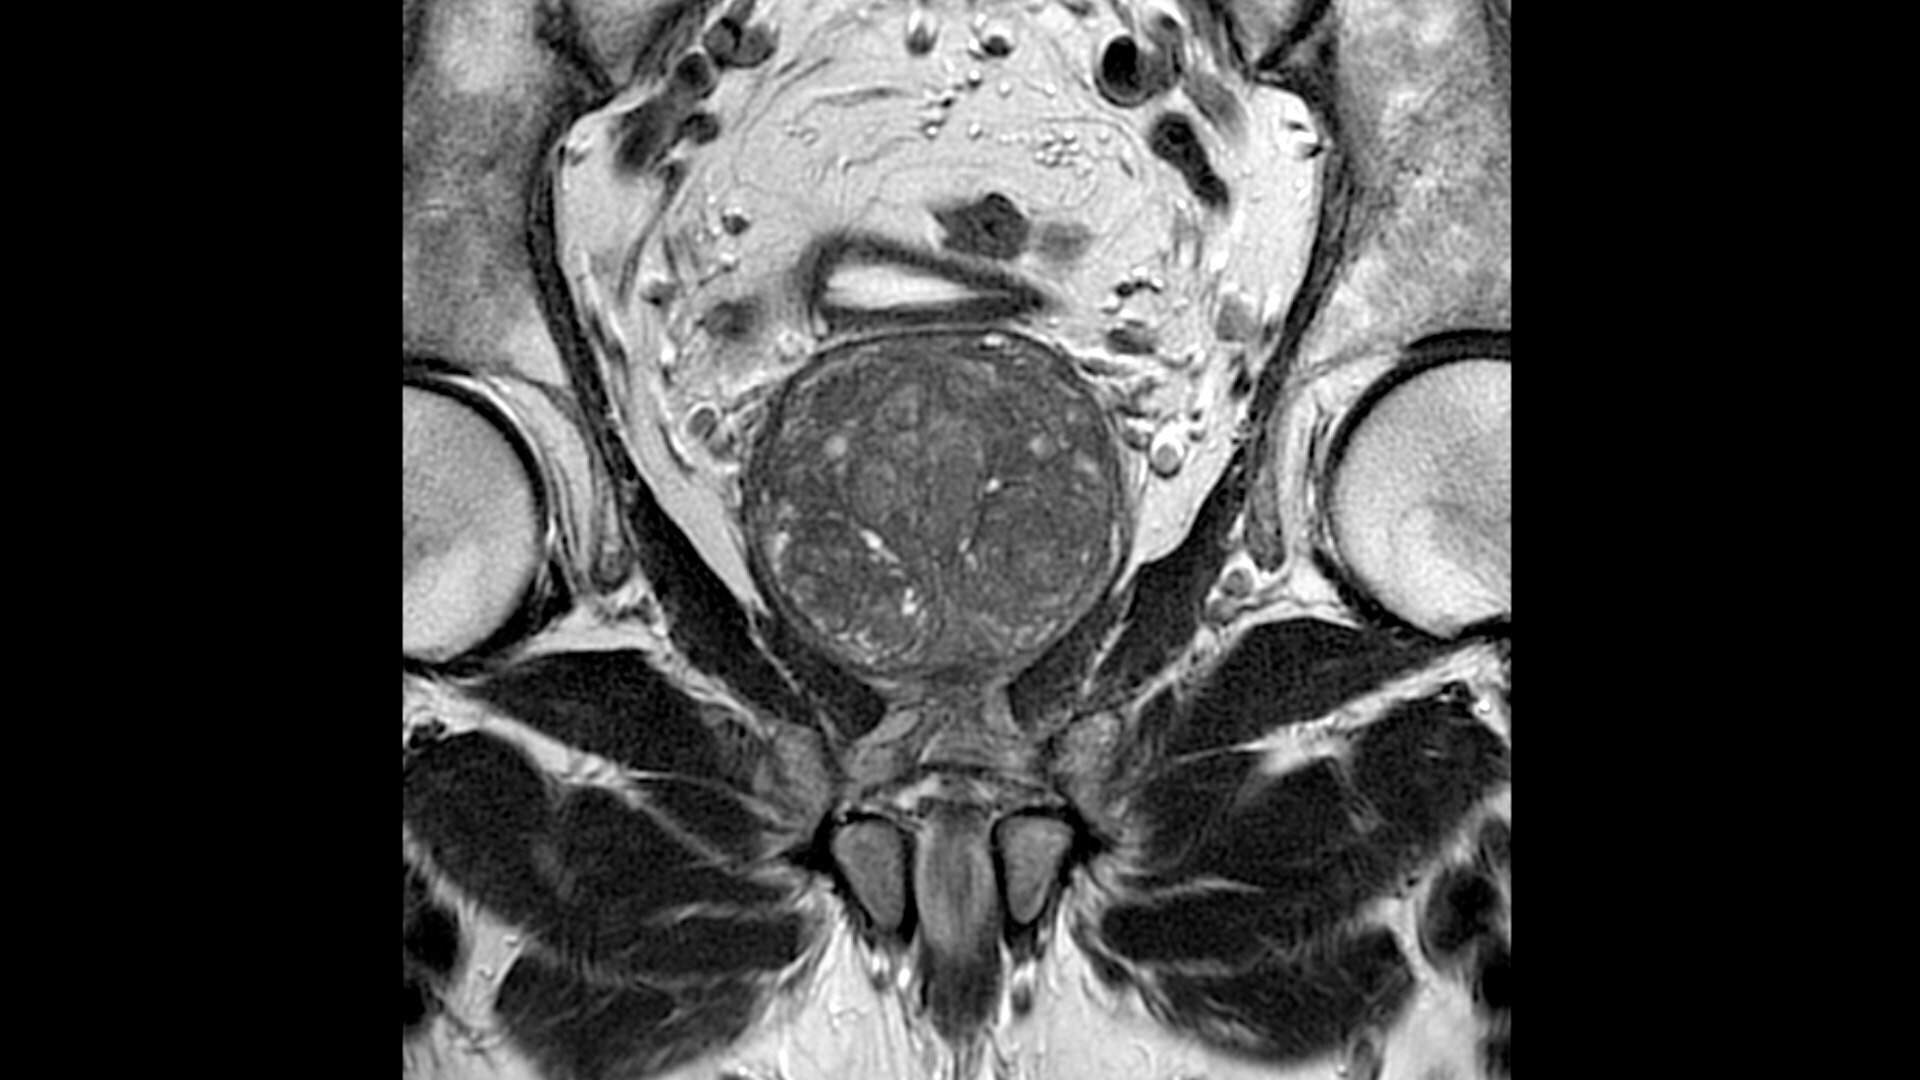

An award-winning industry first in MRI coils. With overlapping, ultra-light, flexible coil elements at their heart, AIR™ Coils deliver an MRI experience that gets closer to your patient, so you get closer to the truth. Representing a new standard in MRI coil technology, AIR™ Coils enable a simplified, faster workflow while maintaining excellent image quality. Scan complex anatomies and complicated conditions in a variety of patient sizes with exceptional results.

The shape of the MRI coil no longer determines what you can do with it. Wrap it around a knee for a complete knee image. Drape it over the patient's body. With an adaptive AIR™ Coil that is light, form fitting and easy to position, it’s the closest you can get to total positioning freedom with 360-degree coverage.

Clinical excellence

Every time we found ourselves starting to compromise, we started over

• Flexible, ultra-low profile design to fit all sizes, shapes and ages

AIRTM MULTI-PURPOSE COILS

• 360 degrees of coverage for MSK imaging

• 38% lighter per channel compared to previous generations of conventional coil technology

• Increased acceleration compared to previous generations of conventional coil technology

• Positioning freedom with previously hard-to-scan anatomies

• 20-ch and 21-ch design to accommodate all patient sizes and anatomies